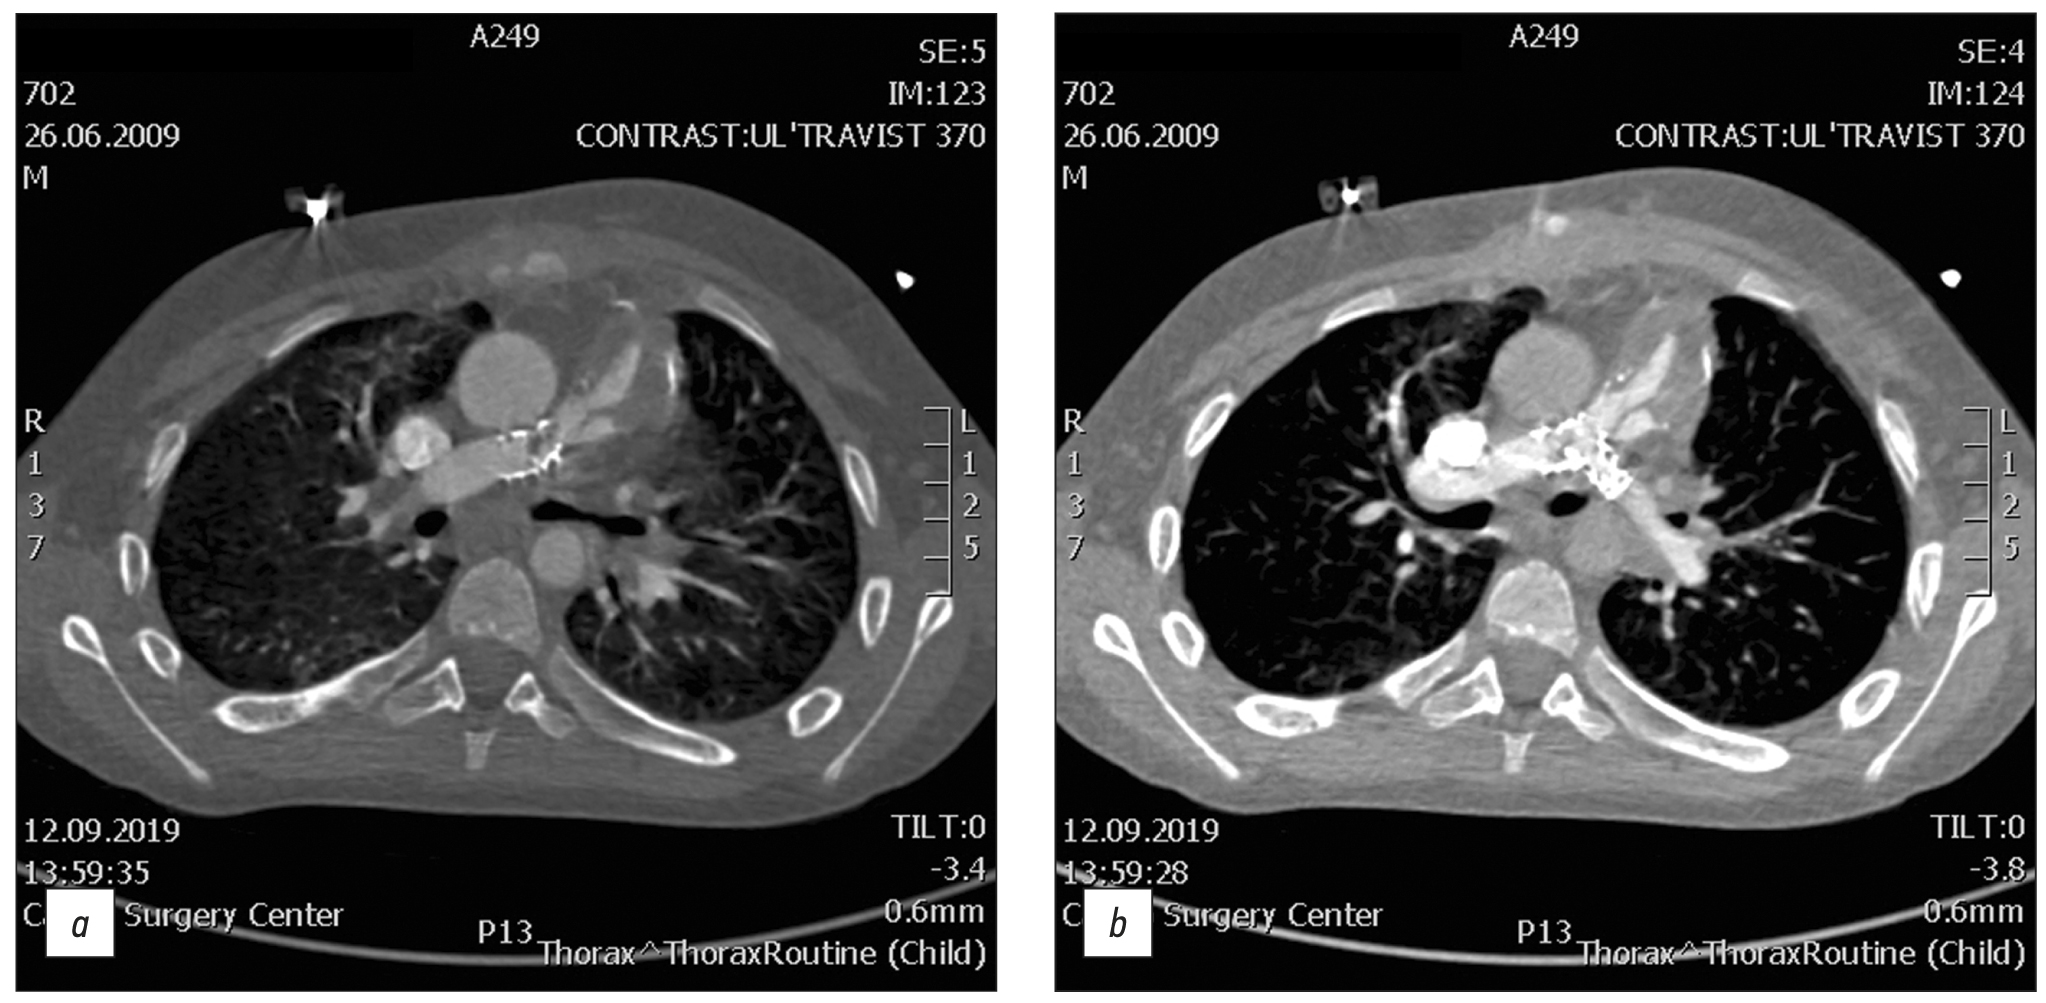

RESULTS: Among the 116 patients who exhibited complications after an repair of Tetralogy of Fallot, 49 had a pulmonary artery stenosis, 92 had a pulmonary artery branch stenosis (56 of them of the left main pulmonary artery branch, and 36 of them of the right main pulmonary artery branch), 8 had a right ventricular outflow tract stenosis, 32 had a ventricular septal defect, 1 had a shunt thrombosis, 12 had a postoperative deformation of the pulmonary artery, 10 exhibited a marked right ventricular dilatation, 2 had an right ventricular outflow tract aneurysm, and 6 suffered from conduit calcification and stenosis. Moreover, patients with left main pulmonary artery branch stenosis had a 6.5 times greater chance of developing an right main pulmonary artery branch stenosis in (p <0.001).

CONCLUSION: The most frequently computed tomography detected complications after a repair of Tetralogy of Fallot were pulmonary artery stenosis and pulmonary artery branch stenosis. Patients with pulmonary artery stenosis and pulmonary artery branch stenosis exhibit no significant differences in terms of age, anthropometric parameters (height, weight, and body surface area), and gender distribution in the presence or absence of different stenosis types (pulmonary artery, right main pulmonary artery branch, or left main pulmonary artery branch). However, an right main pulmonary artery branch stenosis increases the chances of developing an left main pulmonary artery branch stenosis.